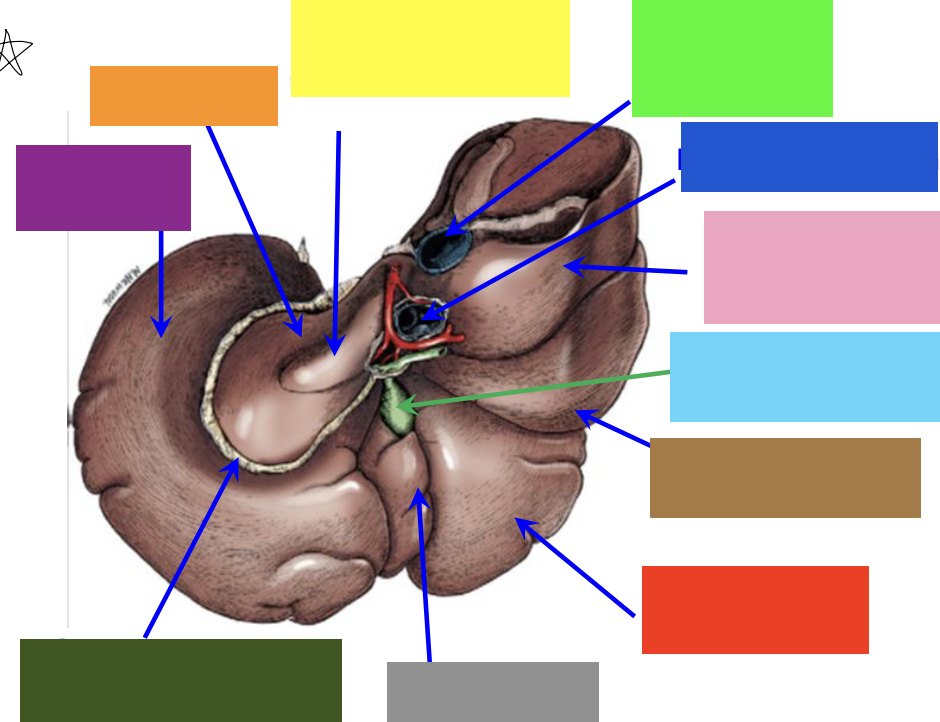

purple box

left lateral lobe

orange box

caudate lobe

yellow box

papillary process of the caudate lobe

neon green box

right lateral lobe

dark blue box

hepatic portal vein

pink box

caudate process of the caudate lobe

light blue box

gall bladder

brown box

right lateral lobe

red box

right medial lobe

grey box

quadrate lobe

dark green box

lesser omentum